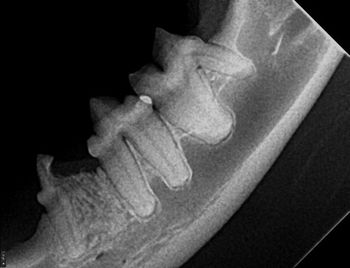

This downloadable handout on tooth resorption for your veterinary clients will help remove some of the mystery of this perplexing but common dental condition.

Tooth resorption is present in almost all our patients, but how do you classify it, and when do you treat it? Veterinary dentist Dr. Mary Volker has answers.